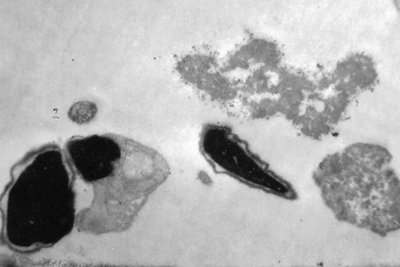

Ảnh chụp qua kính hiển vi đầu tinh trùng người có hình dạng bất thường: Có hai nhân, màng tế bào nhăn nhúm, còn nhiều bào tương (Ảnh trích từ đề tài nghiên cứu của nhóm sinh viên ở Học viện Quân y)